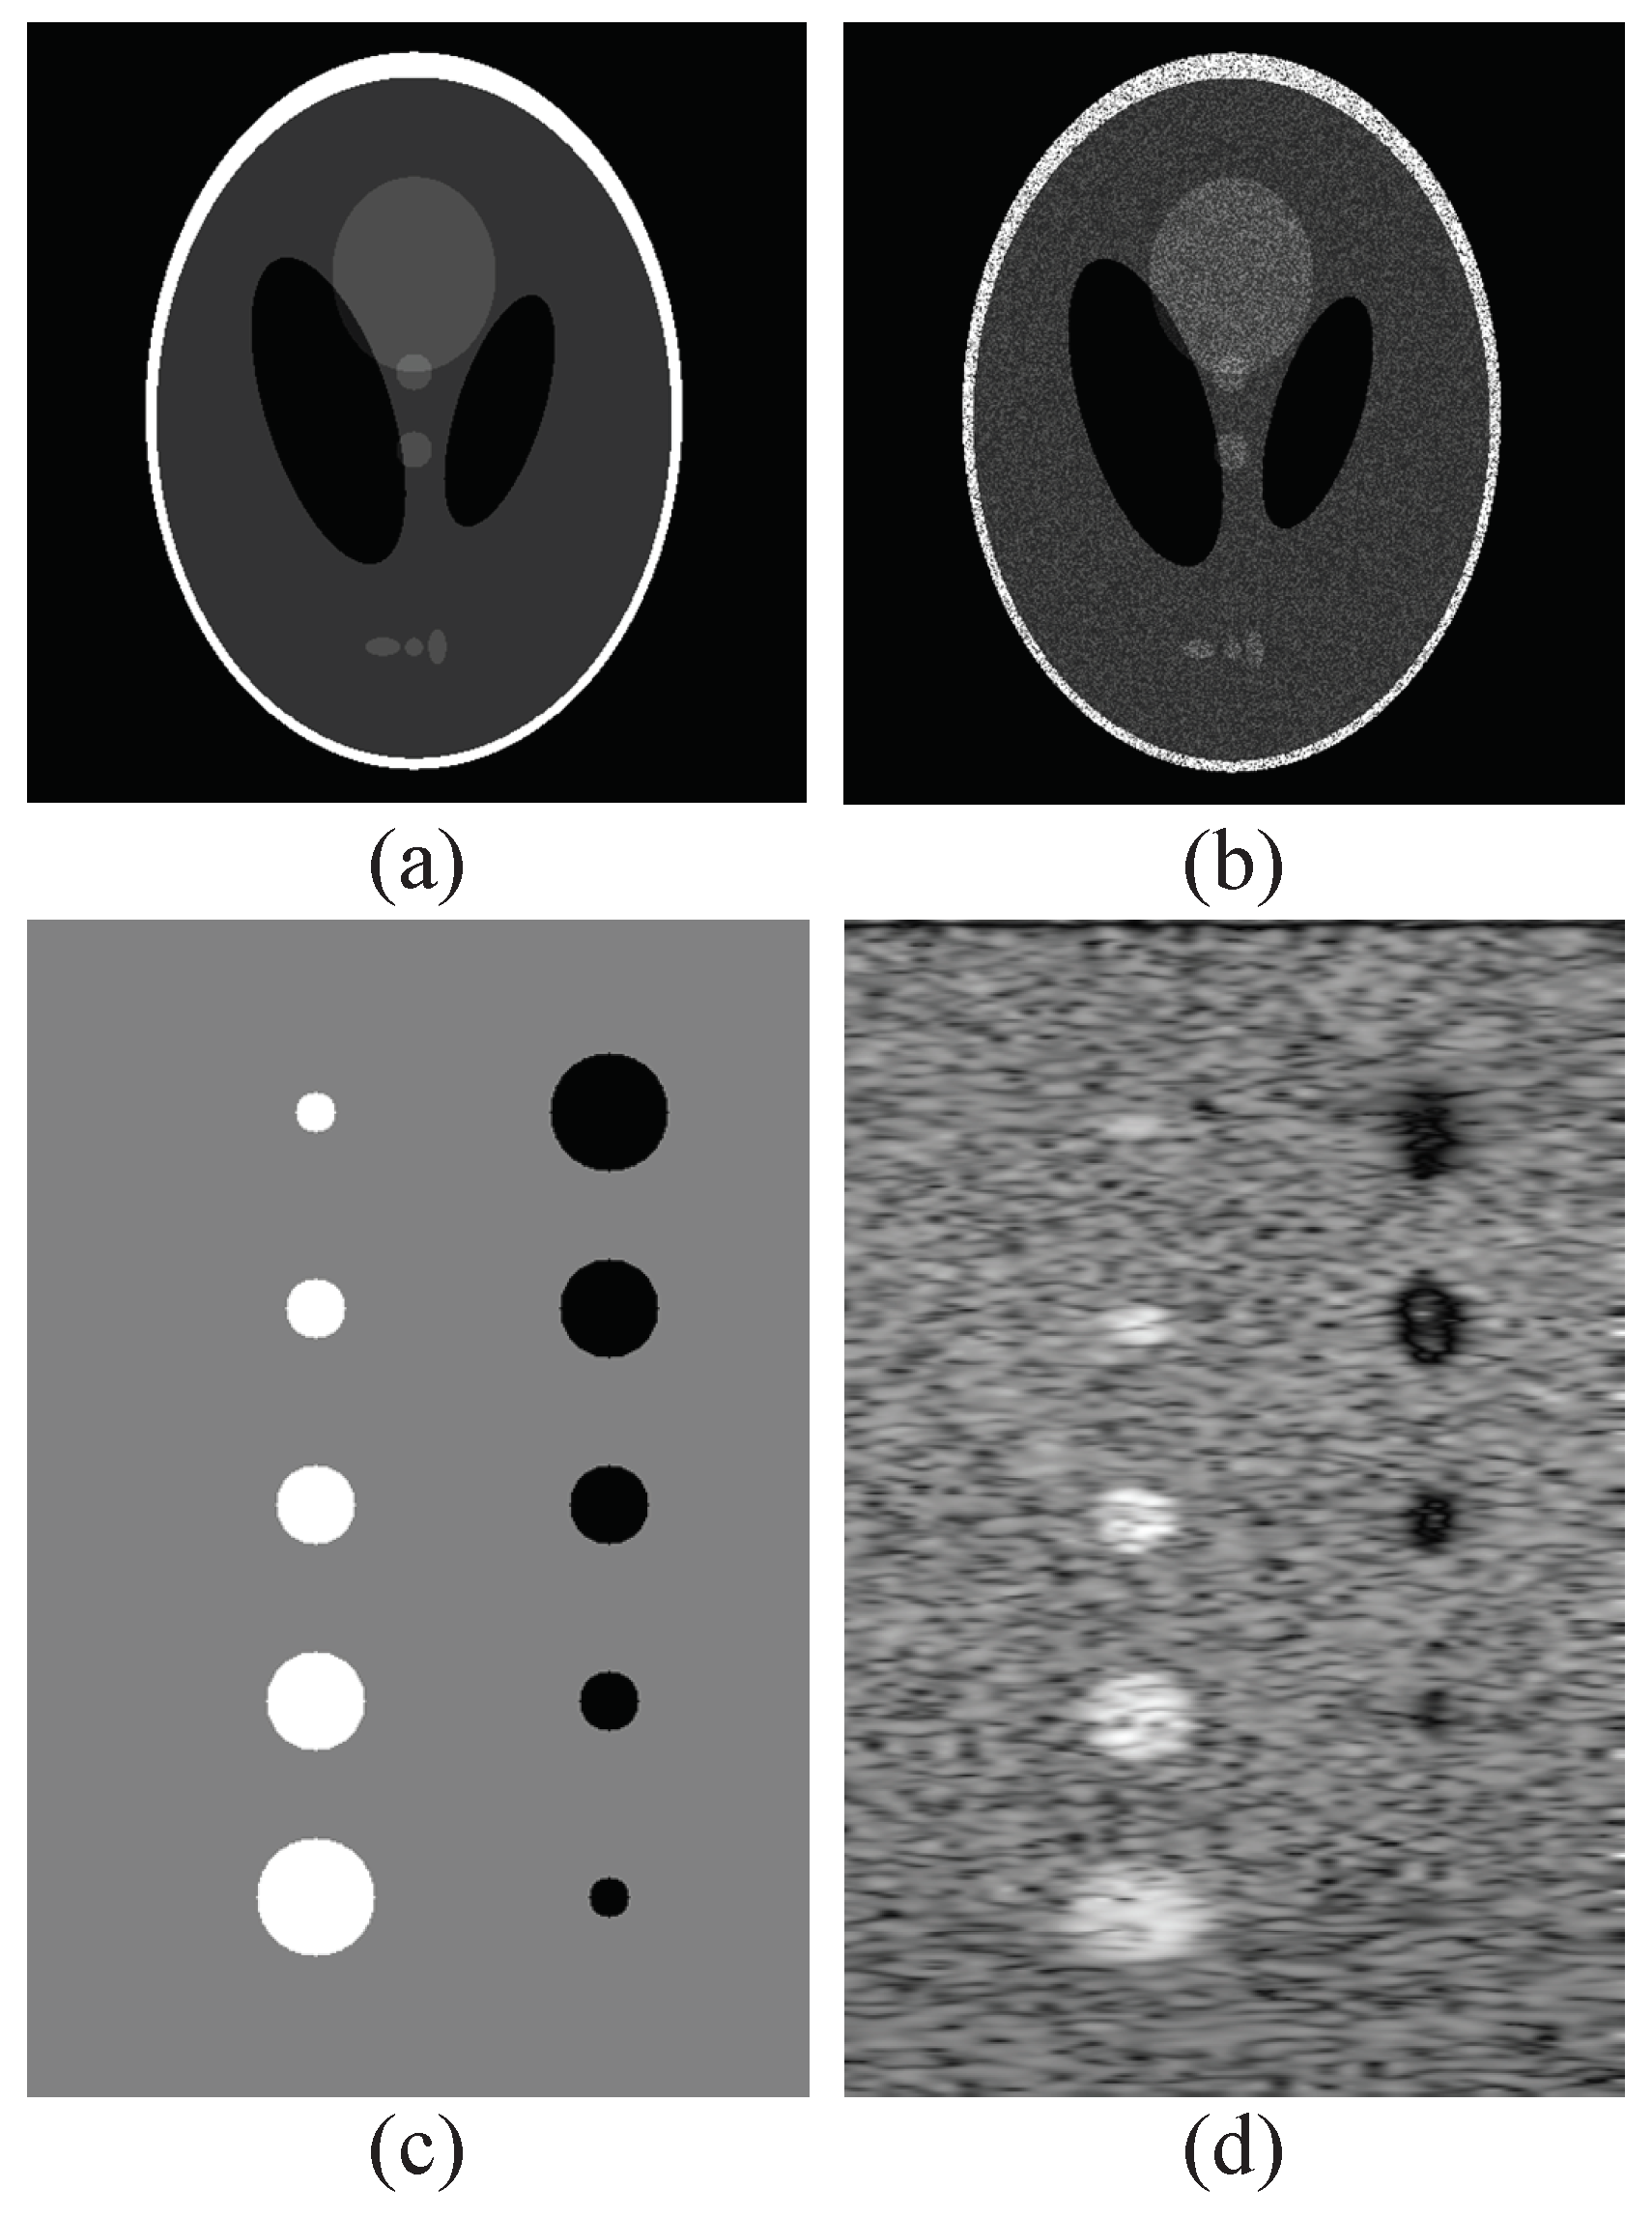

3.2. Tests on Synthetic Images

3.3. Tests on Real Ultrasound Images